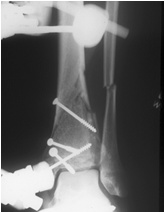

70jähriger Patient mit Pilontrümmerfraktur

seitliche Ansicht

offene Reposition über kleinem Zugang,

Minimalosteosynthese, gelenküberbrückender Hoffmann© II Fixateur.